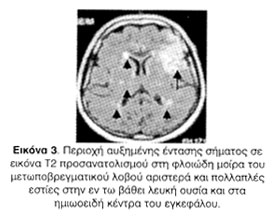

Η μαγνητική τομογραφία εγκεφάλου κατέδειξε πρόσφατη ισχαιμική βλάβη στη φλοιώδη μοίρα του μετωποβρεγματικού λοβού αριστερά και ευρήματα συμβατά με χρόνια ισχαιμική μικροαγγειακού τύπου λευκοεγκεφαλοπάθεια και ανάπτυξη δευτεροπαθούς ατροφίας (Εικόνες 2, 3).